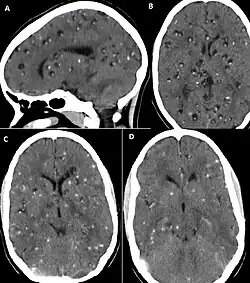

Neuroimaging

CT scans and magnetic resonance imaging (MRI) give objective information about the number and pattern of lesions, the stage of healing, and how the immune system is responding to the parasites.[19] MRIs are better for evaluating different spatial planes and provides clearer images, which helps in identifying small lesions at the back of the brain or near the skull that may be missed on CT scans. CT scans are more sensitive at detecting calcium buildup in the brain due to its ability detect calcifications in the brain.[30]

Live vesicular cysts are small, round lesions with little swelling around them and do not need contrast for imaging. The tapeworm head (scolex) usually appears as an asymmetric nodule inside the cysts. Multiple live cysts with these heads corroborate the diagnosis. Once the cysts begin to break down (colloid cysts), their borders become unclear, they are surrounded by swelling and exhibit significant ring or nodular contrast enhancement. Calcified cysticerci are shown on CT scans as non-enhancing hyperdense nodules without swelling.[20]